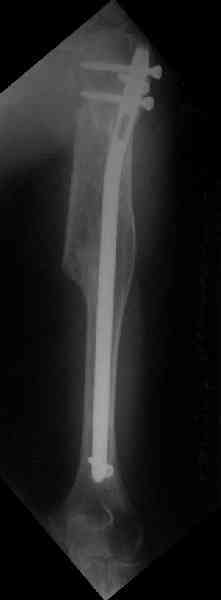

Здесь нет необходимости в серкляже. Вмешиваться на промежуточных отломках приходится, если есть угроза перфорации кожи, или промежуточный отломок попал в фасцию, как пуговица в петлю. В приложении сегментарный оскольчатый перелом плеча в проксимальном отделе, фиксированный больщеберцовым стержнем. Как видите, обошлось без серкляжа. Функция полная.

Это укороченный большеберцовый стержень, которые делает предприятие "ЦИТО".

Доступные на тот момент гвозди для плеча имели худшие возможности фиксации в коротком проксимальном отломке.